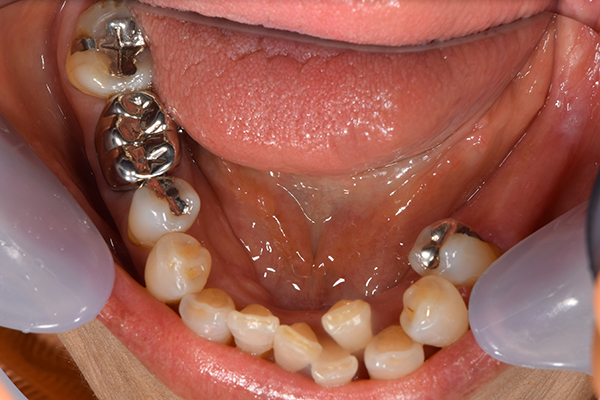

上下の入れ歯が外れやすくなったということでいらっしゃいました。 顎の骨はしっかりしていましたので、精密な型取りさえすればしっかりした入れ歯がつくれると思いました。 また下には6本歯が残っていましたが、虫歯になっている歯もありました。 かぶせ物のなかで大きな虫歯があった歯があり、1本だけ残せない状態でした。

上の入れ歯は確かに吸着は甘くなっていました。 また下の入れ歯はバネの一部が壊れており、安定感がなくなっていました。

完成した入れ歯とかぶせ物です。 入れ歯への寛容度が高い患者様でしたので、 金属は使用せず、プラスチックのみで上は仕上げました。 下顎も歯は1本減ってしまいましたが、しっかり 入れ歯が維持できる様な構造にしました。

お口の中に入れた状態です。 見た目も最初とほとんど変わることなく作成できました。 維持や吸着に関しても問題ないようでした。